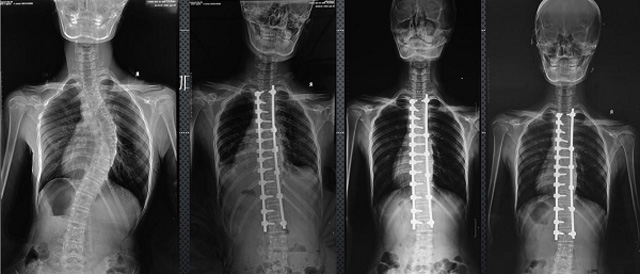

(7)全身拼接功能對有較大尺寸全脊柱拼接圖接桂成金下股分成幾次拍攝,再經(jīng)過秋件開在骨科開展的全脊柱畸形矯治工作中,雖然CT. MRI也能獲取全脊柱影像,接圖像,以便于長度、角度、力線等測量和察脊柱在重力情況下但不能進(jìn)行立位檢查,無法觀全景觀察。全身拼接功能是高等級DR攝取患者立位全下的功能狀態(tài)圖像,因此采用動態(tài)醫(yī)院特別看重的動態(tài)DR功能之一。注:圖中Cobb脊柱正側(cè)位圖像是首選的檢查方法角度的大小是反映側(cè)彎嚴(yán)重程度的一個標(biāo)準(zhǔn)。